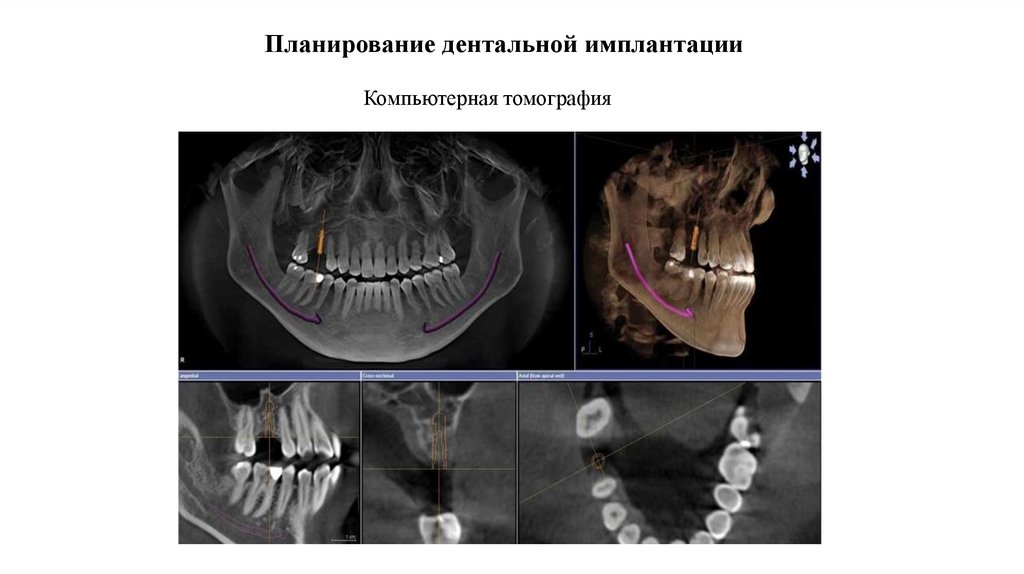

Планирование дентальной имплантации

Компьютерная томография

Компьютерная томография. Биотипы костной ткани